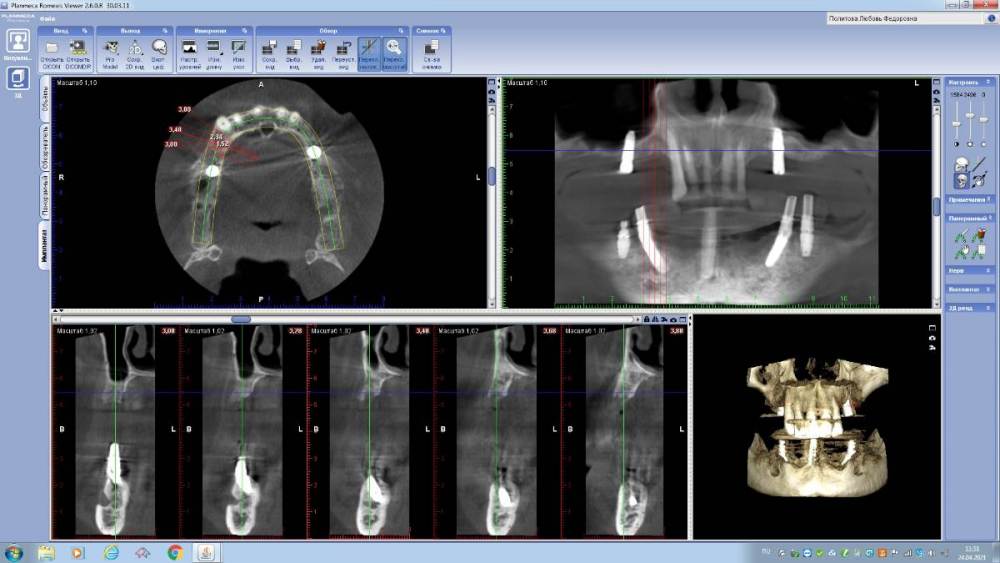

annda Опубликовано 29 апреля, 2021 Поделиться Опубликовано 29 апреля, 2021 (изменено) Интересующая область-14. Пациентка обратилась для протезирования дефектов полости рта.Было предложено удалить весь верх и низ.На верху было предложено все на 6,внизу все на 4х,но решила сделать все на 5(а вот так вот). Поступил категорический отказ удалять верхние передние зубы(на приеме подвижность 1-2й степени).Тогда как альтернатива предложен съемник на локаторах как временный вариант(с тайной мыслью-"вот поносишь и все равно придешь за первым вариантом") На операции одномоментное удаление боковых верхних и низа,установка имплантатов,формики и нагрузка в соответствии с торками.Дикий дефект в области 14 просто откюретажили до костной ткани,грануляции вырезали. Через 4 месяца приносит новую КТ.Я просто онемела.Зубы на верхней челюсти неподвижны от слова совсем...Вот что это было и есть?? Изменено 29 апреля, 2021 пользователем annda 1 Ссылка на комментарий

Дмитрий Л. Опубликовано 29 апреля, 2021 Поделиться Опубликовано 29 апреля, 2021 Не могу поверить...) разные срезы или настройки кт. Ссылка на комментарий

annda Опубликовано 29 апреля, 2021 Автор Поделиться Опубликовано 29 апреля, 2021 По протезке не было ничего, от слова совсем. Даже кривые настройки КТ не могут так исказить картину:))Срезы одни и те же , видны на обоих снимках, зубы центральные принадлежат одному человеку. Кстати, 68 лет от роду... Кость уже пощупала фрезой, абсолютно полноценная костяка... Ссылка на комментарий